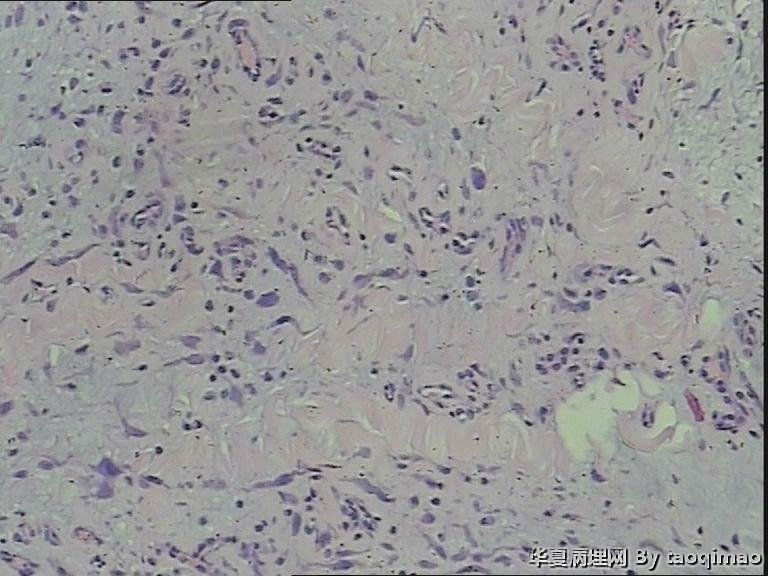

胸壁肿物

结节性筋膜炎+神经节样细胞+肌肉浸润=增生性肌炎。

粗略看了下,对软组织病变不是很在行,初步印象是增生性肌炎,几个图像里小血管内皮肿胀,周围炎细胞浸润,结合临床除外血管炎或者自身免疫相关疾病。

男,54岁,右侧胸壁肿物发现1月余,取材:灰白色不规则组织一块2*1.7*0.5cm,剖面实性灰白色,质韧。